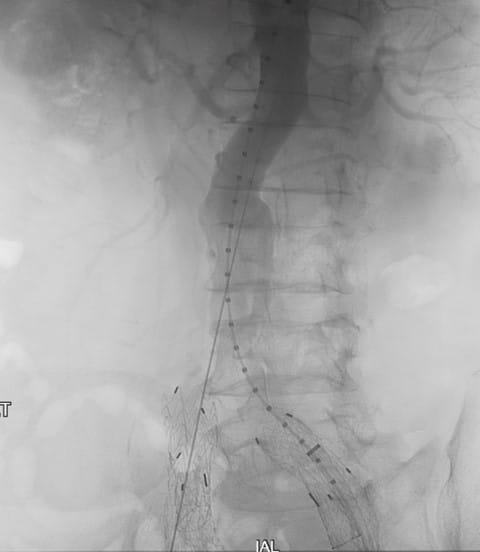

A 76-year-old male presented to UPMC for evaluation of aortoiliac aneurysm disease. His past medical history is also significant for mild emphysema, hyperlipidemia, lung and prostate cancer, and he has no family history of aneurysmal disease or connective tissue disorder. He is without symptoms of cardiac ischemia or peripheral claudication. His preoperative CT scan demonstrated the presence of a small infrarenal abdominal aortic aneurysm measuring 4.8cm, and bilateral large common iliac artery aneurysms, measuring 4cm and 3.8cm on the right and left, respectively. The internal iliac arteries were patent bilaterally (Figure 1 and 2). He underwent endovascular repair of his abdominal aortic aneurysm with placement of bilateral iliac branch endoprostheses (Gore Medical, Flagstaff AZ) for his bilateral common iliac artery aneurysms via percutaneous bilateral common femoral artery access (Figures 3-6). The patient tolerated the procedure well and was discharged on post-operative day two.

Figure 4: Positioning of the left iliac branch endoprosthesis with cannulation of the internal iliac limb